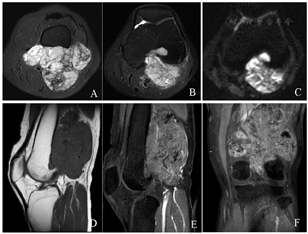

影像学检查:左膝关节计算机断层扫描(CT)显示左腘窝肌间隙内见分叶状软组织肿物,边界尚清,密度不均匀,内见结节状钙化灶,邻近股骨受侵,骨皮质变薄(图1)。左膝关节磁共振成像(MRI)显示左腘窝内一巨大不规则肿块,大小约9.1 cm×6.0 cm×10.0 cm,信号混杂,以T1加权像低信号、T2脂肪抑制序列高信号为主,弥散加权成像(b=800 s/mm2)呈不均匀高信号,增强扫描肿块明显不均匀强化,邻近股骨下端可见类似强化灶(图2)。

发生于涎腺区的肌上皮瘤的影像学报道诸多,而关于软组织肌上皮瘤的影像学报道极少[11]。软组织肌上皮瘤的影像学表现缺乏特异性及典型特点,针对本例病灶影像学表现,并结合相关文献报道,总结软组织肌上皮瘤影像学特点如下:(1)发生于四肢的软组织肌上皮瘤,因肌间隙空间较松弛,给肿块提供了生长空间,因此肿块体积多较大,平均直径多>5 cm,大多呈分叶状,且病灶数目可能会大于2个。(2)肿块边界比较清晰,与周围肌肉及骨骼分界明显,周围血管及神经纤维组织受压推移改变,部分患者邻近骨骼肌可见肿瘤组织浸润。(3)病灶密度/信号不均匀,CT多表现为软组织密度肿块,内可见点状或结节状钙化灶,而MRI则表现为T1WI低信号、T2WI高信号为主肿块,DWI呈稍高信号,增强检查呈明显不均匀性强化,肿块内部少见囊变坏死区。(4)软组织肌上皮瘤属于良性肿瘤,但是肿块具有一定的侵袭性及复发性,术后容易原位复发,局部复发率为15%~18%,且远期复发多见,并且复发病灶的范围及数目均较前明显进展[1]。